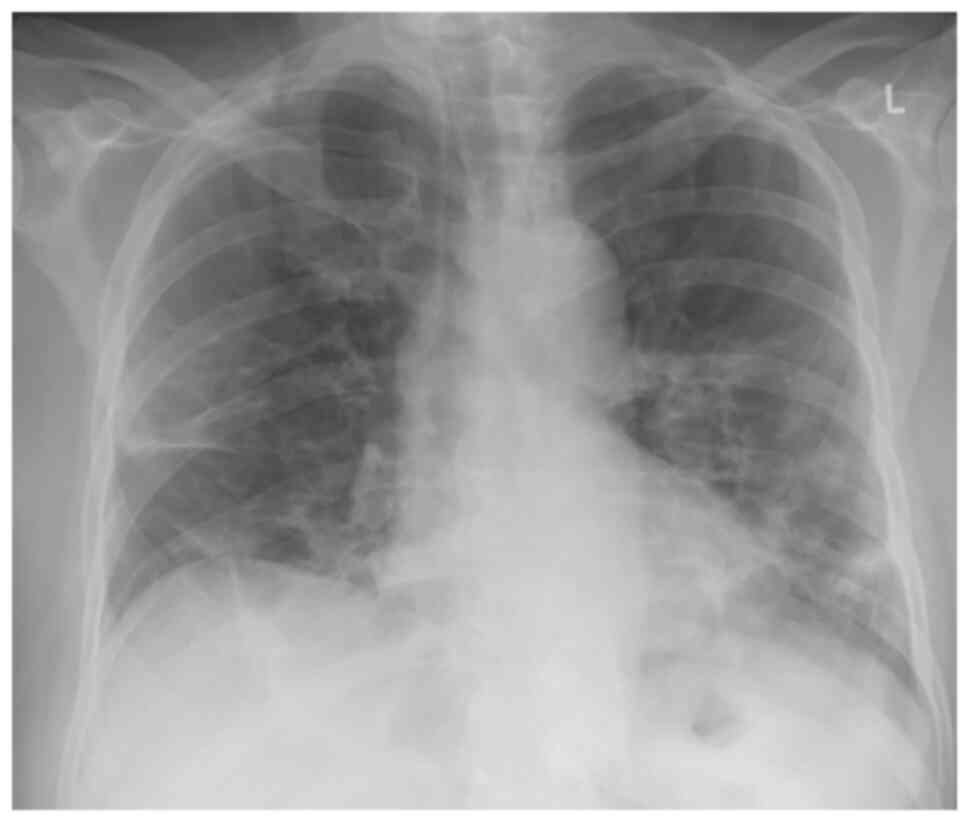

The analysis of arterial blood gas revealed partial pressure of oxygen (pO2) levels of 54 mmHg, pressure of carbon dioxide (pCO2) levels of 41 mmHg, pH 7.47 and HCO3- at 29.8 mmol/l in room air. An X-ray of the chest revealed patchy diffuse opacities in both lower lung lobes (Fig. 1).

Figure 1

Chest X-ray illustrating patchy diffuse opacities in both lower lung lobes.